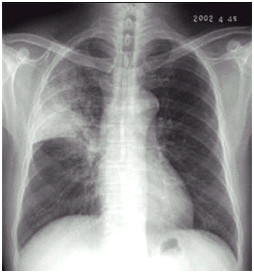

02卷-4.男性,24歲,發(fā)熱、咳嗽、咳痰4天。診斷(本題滿分2.00分)

A.右上肺不張

B.右上胸膜肥厚

C.右上肺癌

D.右上肺炎

本題答案:D

題目解析:

【該題針對“ X線-肺癌 ”知識點進行考核】